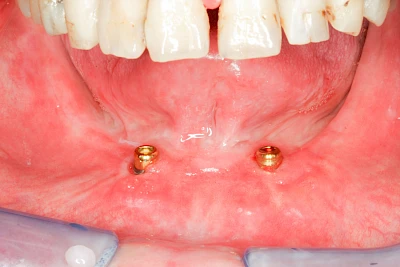

Implantate: Prothesen

Bei herausnehmbaren Prothesen werden Implantate eingesetzt, um den Halt und den Tragekomfort der Prothesen zu verbessern. Dazu kommen verschiedene Verbindungselemente zum Einsatz:

- Teleskope

- Kugelköpfe

- Tellerförmige Lokatoren

- Stege

- Magnete (selten)

Neben rein implantat-getragenen zahnärztlichen Versorgungen werden bei herausnehmbaren Prothesen Implantate auch in Sinne einer "strategischen Pfeilervermehrung" ergänzend zu eigenen Zähnen zur Verankerung eines Zahnersatzes genutzt.

Varianten zur Verankerung von abnehmbarem Zahnersatz auf Implantaten